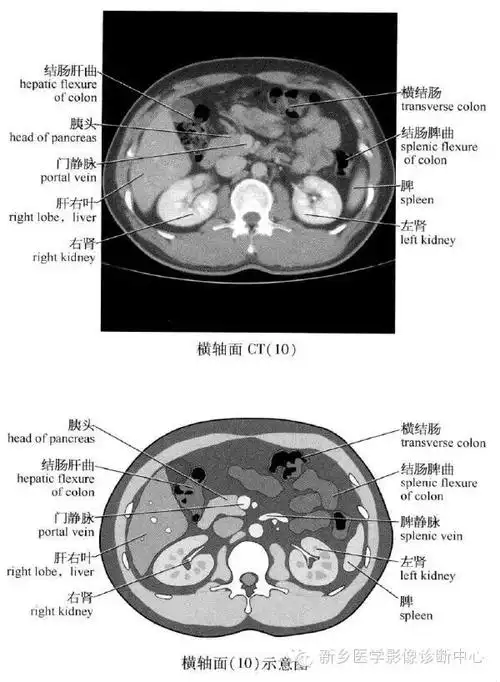

史上最全腹部横断位解剖详细标注

点滴积累,成就影像专家.腹部ct断面解剖